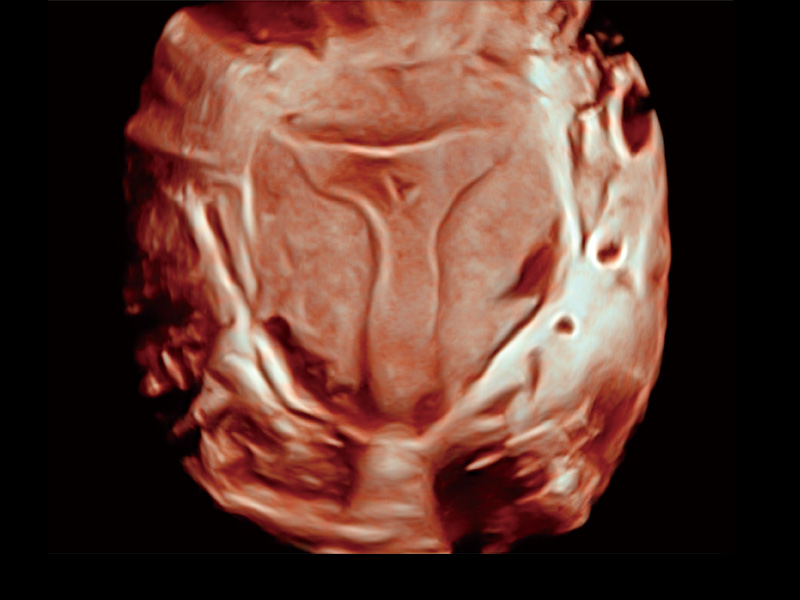

腔内容积探头

腔内三维成像技术获得显著提升,超大扇角在满足日常基础扫查的同时,支持卵泡自动测量及多种三维渲染模式,为您提供更多的诊断信息,尤其是在子宫畸形的诊断,内膜及肿瘤占位观测中起到了重要的作用。

中央型宫腔粘连

单角子宫

子宫内膜息肉